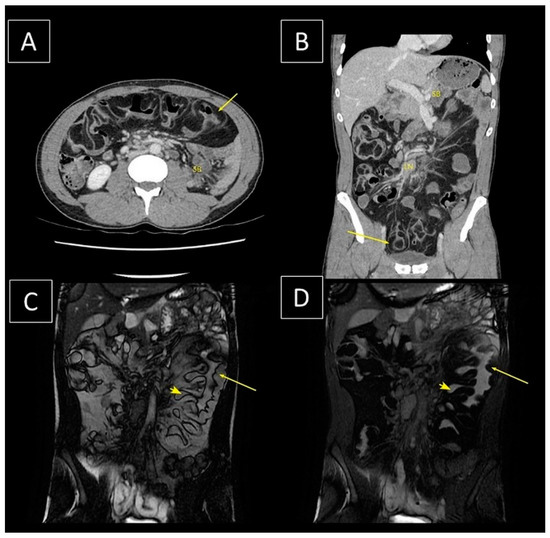

- Komagata, T.; Takebayashi, S.; Hirasawa, K.; Fukawa, T.; Arai, M. Extensive Lipomatosis Of The Small Bowel And Mesentery: CT and MRI Findings. Radiat. Med. 2007, 25, 480–483. [Google Scholar] [CrossRef]